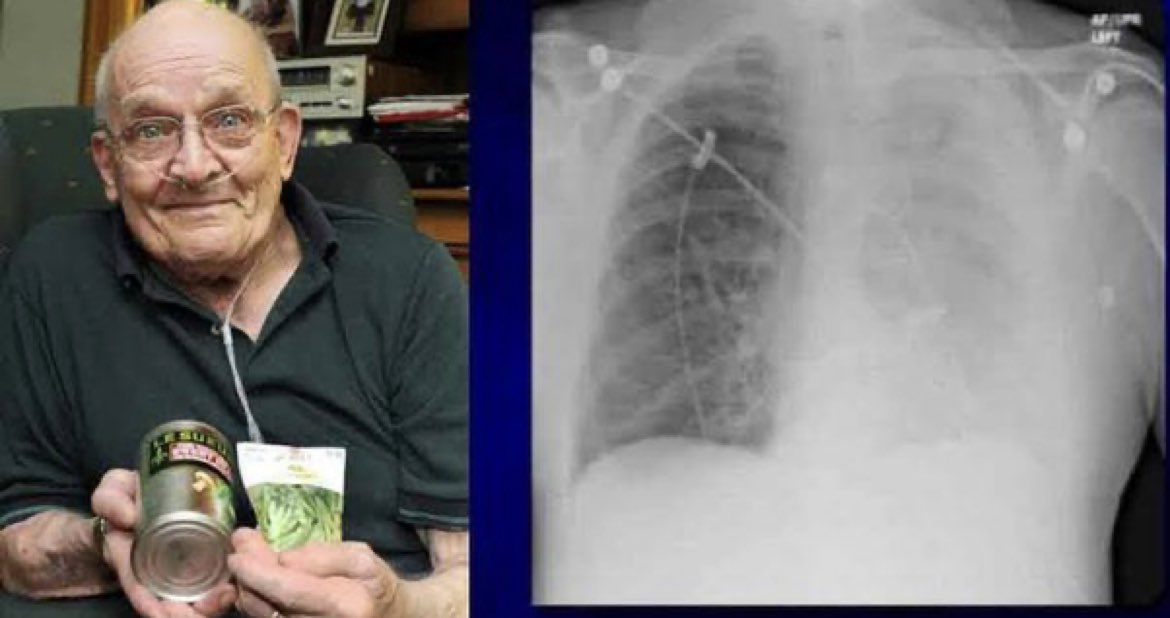

كان رون سفيدن ، البالغ من العمر 75 عامًا من ماساتشوستس ، يعاني من ضيق في التنفس لمدة شهرين. ثم بدأت حالته تتدهور. بدأ في السعال بلا انقطاع ذات يوم. كان ذلك عندما علم أنه شيء خطير.

تم نقله إلى المستشفى ، وقام الأطباء بأخذ صورة بالأشعة السينية. ووجدوا أن إحدى رئتيه قد انهارت وشوهدت بقعة صغيرة على الأشعة السينية كان سفيدن متأكدًا الآن من أنه مصاب بالسرطان. لقد انتظر فقط حتى يتحدث الأطباء.

تبين أن اختبار السرطان كان سلبيا. وبدلاً من ذلك ، وجد الأطباء نبتة بازلاء تنمو من رئتيه. افترض الأطباء أن حبة البازلاء قد سقطت في الحفرة الخطأ في وقت ما

يبدو أن الظروف الدافئة والرطبة داخل الرئة جعلت منها مكانًا مثاليًا لنمو نبات البازلاء. بعد عملية جراحية بسيطة إلى حد ما ، تمت إزالة نبات البازلاء بطول 1.25 سم من رئته.